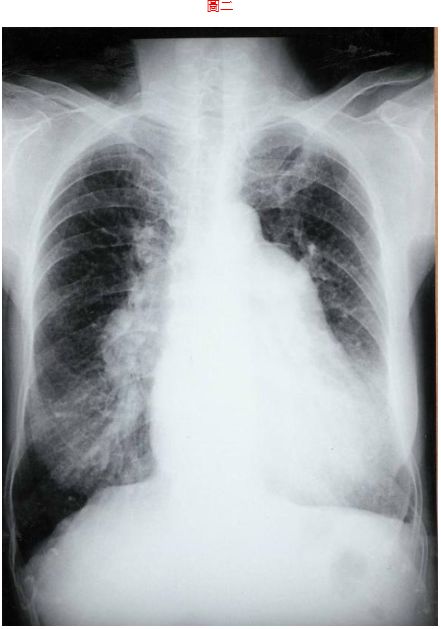

2. 75歲女性,從年輕時就常有感冒,這次來院主訴兩週來持續性呼吸困難。病人40歲時因感冒求診時,基層醫師就告知有心臟病。結婚後都因流產未生孩子,最近兩週有運動性呼吸困難,尚有食慾不振、拉肚子及腳腫。理學檢查血壓130/70 mmHg、76次/分,規則跳動,頸靜脈怒張,肺無囉濁音,但有異常心音,有輕微的肝腫。其心電圖(圖一 )及胸部X光(圖二 )如附頁;就心電圖紀錄,這位75歲老婦最顯著之異常有:(1). 右心室擴大(2). 左心室擴大(3). 所有心房心室都擴大(4). 肺動脈高血壓(5). 主動脈高血壓 (A) 1+2 (B) 1+3 (C) 1+4 (D) 1+5 (E) 2+4